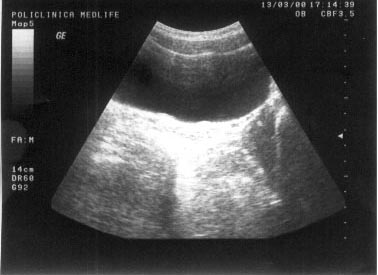

Imaginea transsonica

Structurile lichidiene (sangele, bila, secretiile digestive, continutul chistelor, ascita, colectia pleurala) sunt strabatute de catre ultrasunete in totalitate, fara a exista nici un fel de reflexii pe traseul acestora. Imaginea ecografica, fiind expresia unei "lipse de ecouri", va avea aspectul opus structurilor ecogene, respectiv culoarea neagra. O structura lichidiana este definita in ecografie prin termenul de transsonic.

Exemple:

structuri transsonice normale: colecist, vezica urinara, lumen vascular;

structuri transsonice patologice: chistul, continutul necrozat al unui abces sau al unei tumori maligne.

Figura 1. Vezica urinara

Figura 2. Chist renal stang situat in treimea medie

Figura 3. Chist ovar drept

Figura 4. Chist hepatic